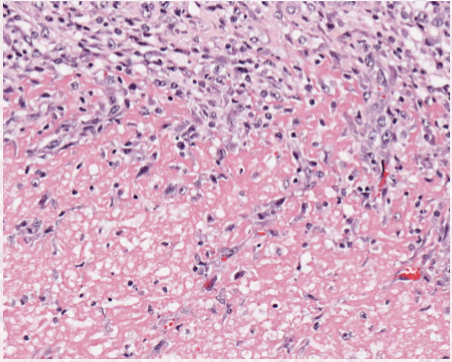

Describe the cellular morphology of necrosis

increased cellular eosinophilia

nuclear shrinkage + increased basophilia (pyknosis)

fragmentation of nucleus (karyorrhexis)

loss of nuclear basophilia (karyolysis)

describe steatonecrosis

necrosis of adipose tissues, between lytic and coagulative.

Describe gangrenous necrosis

subtype of lytic

occurs in distal limbs or dependant portions of organs

dry = vascular damage

wet = bacterial proliferation

describe fibrinoid necrosis

specific form of lytic necrosis, occurs during vascular damage

intramural () accumulation of fibrin, other proteins and immunocomplexes in vessels ( associated with vasculitis)